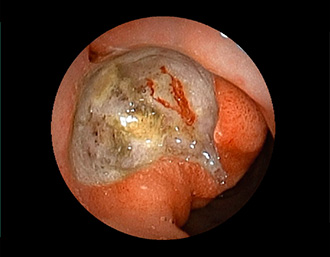

症例3:十二指腸潰瘍(53才男性)

1年前からの慢性胃痛を主訴に当院受診。十二指腸球部前壁に深くて大きな潰瘍(Stage A1)があり、潰瘍底は厚い白苔に覆われ、一部白苔のはみ出しを認める。潰瘍周囲粘膜は浮腫を伴っている。ボノプラザンフマル酸塩投薬で治療開始しました。

(通常画像)